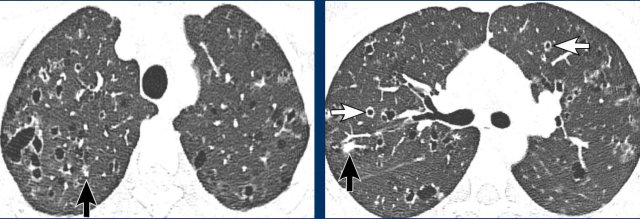

Findings

There are a few thin-walled cysts in combination with nodules (white arrow) and cavitating nodules with a cheerio sign (black arrow).

Continue with the next images...

As always we want to have a good look at the pleural recesses.

We can skip the diagnosis LCH, because the pleural recesses are involved.

In a non-smoker this diagnosis was already unlikely.

High in the differential diagnosis is metastatic disease.

However no malignancy was found.

This proved to be benign metastatic leiomyoma.